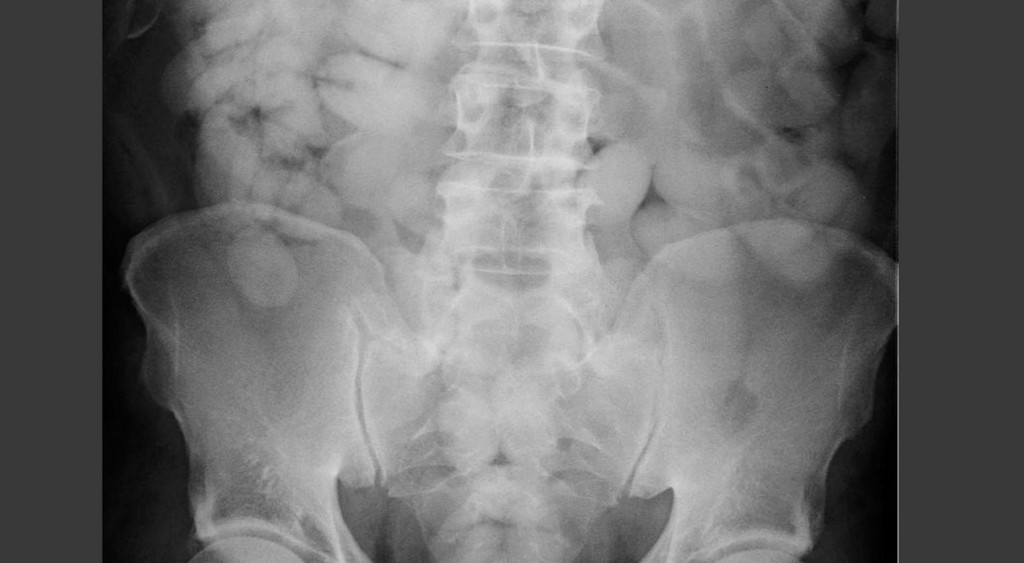

▲英國邊境檢察官員表示,不少毒品走私販子為了報酬,鋌而走險的將一包包毒品吞進肚內,就為了要闖關成功。(圖/翻攝自英國衛報)

邊境檢查官員表示,這些毒品販子一次多半吞下高達80到110包的毒品,這些毒品有的裝在保鮮膜裡,有的裝在汽球或是保險套裡。雖然販毒一次可賺大約1000到1500英鎊(約48910台幣到73370台幣),但很多時候黑道幫派會利用暴力恐嚇,運毒份子也不見得能獲得高額的報酬。

一名來自波蘭的毒品走私販子、51歲的阿當斯基(Jaroslaw Adamski)告訴邊境檢察官員,會接觸毒品是因為,一名同樣來自波蘭的同鄉告訴他,只要吞下一包毒品並運毒成功,就能夠賺取11英鎊(530台幣)的酬勞。阿當斯基吞了數十包後,以為自己神不知鬼不覺,但還是被查獲,根據邊境檢查官員表示,他的身體當時共有高達950公克的毒品,市值就要15萬英鎊。